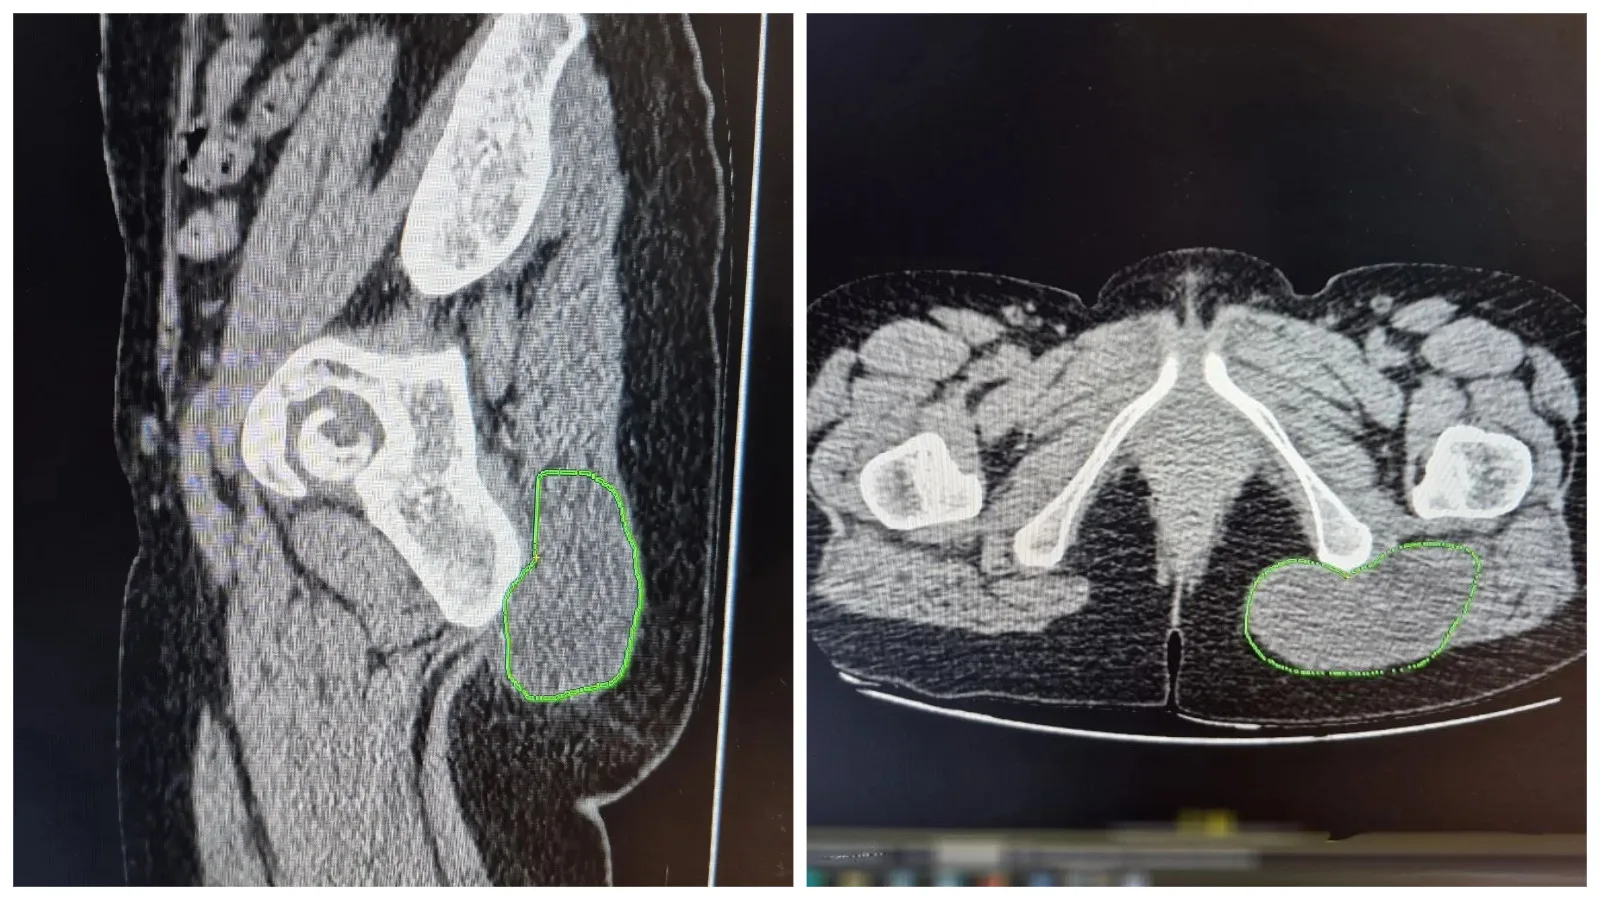

В Балаковской городской клинической больнице выяснили: это не жировик, а злокачественное новообразование из жировой ткани. Женщину прооперировали, есть шансы на полное выздоровление.